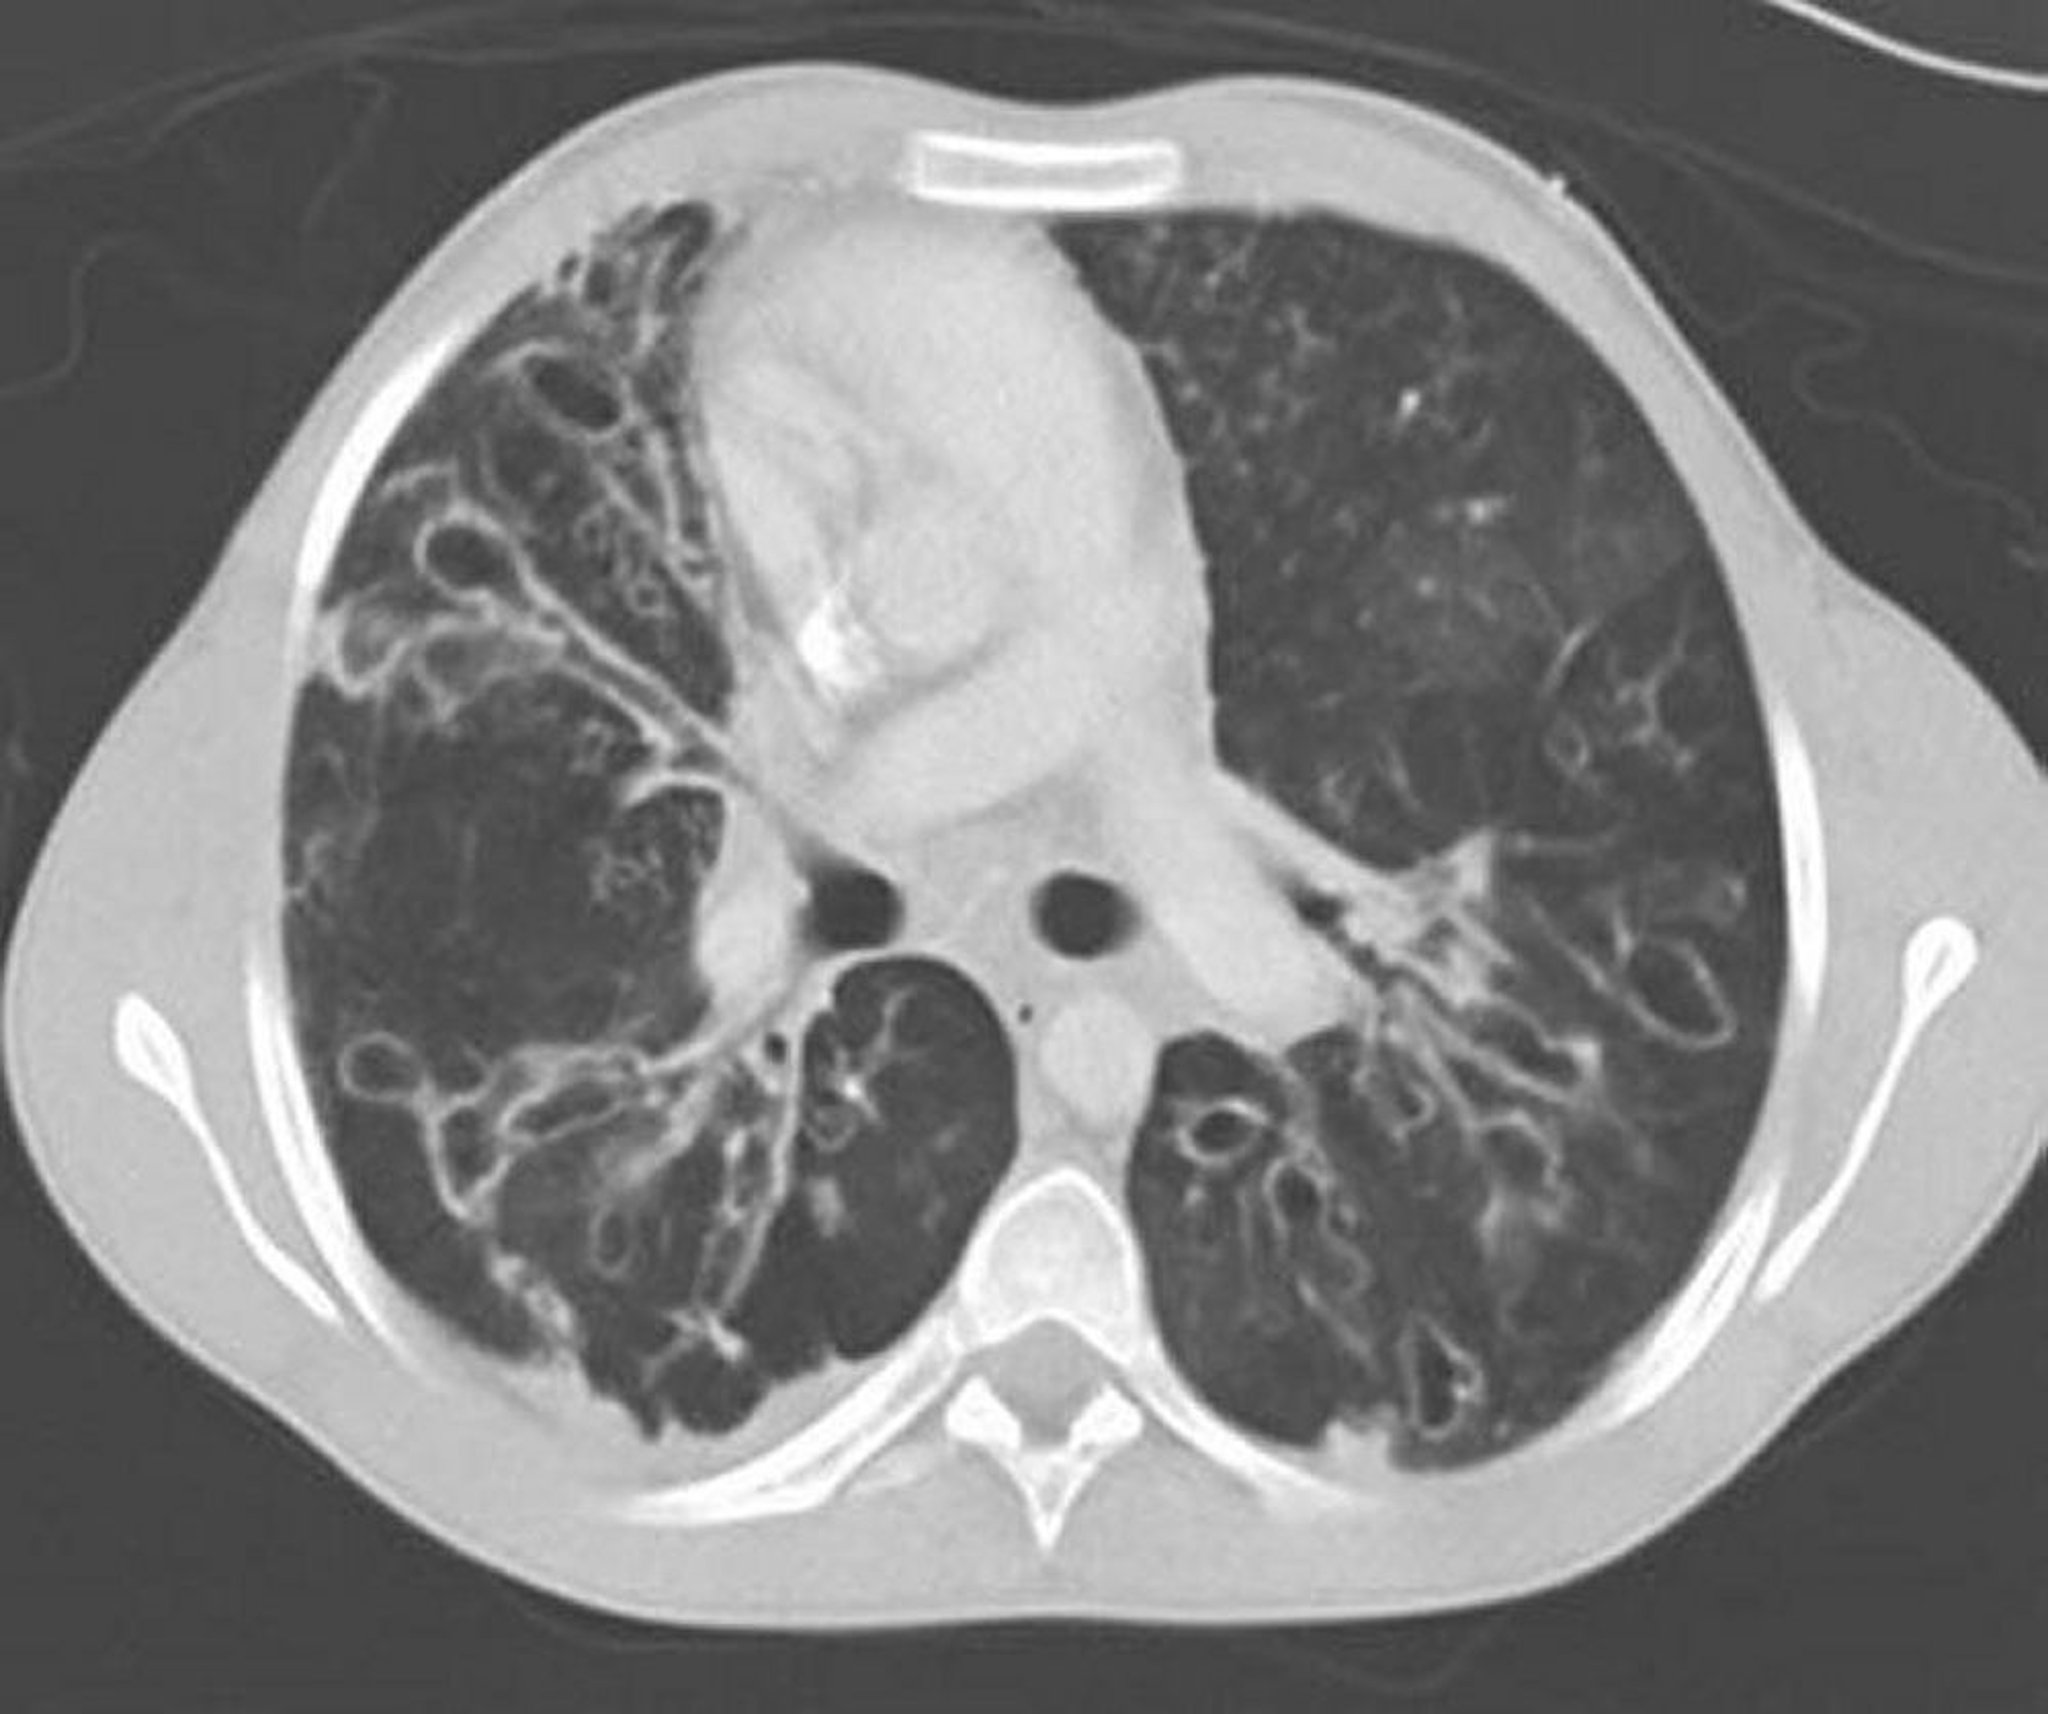

Аллергический бронхолегочный аспергиллез (бронхоэктазия)

Контрастная КТ грудной клетки демонстрирует тяжелый бронхоэктаз в средних зонах легкого с сильно расширенными и эктатическими дыхательными путями и кистозными изменениями. Эктазия дыхательных путей характеризуется соотношением дыхательных путей к прилегающим сосудам > 1.